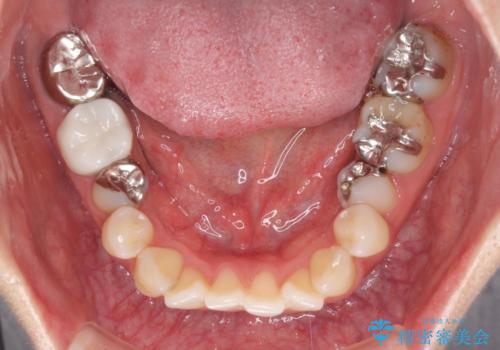

総合歯科治療 矯正治療と失活歯のセラミック補綴治療

- 失活により変色した歯と不揃いな口元を気にして来院された患者様です。

口元をインビザラインにより歯列を整え、その後に失活している奥歯をオールセラミッククラウンにて補綴治療することとしました。

長時間のマウスピース装着と、患者様自身でのゴムかけに協力いただき、自然な口元に仕上げることができました。

気になっていた変色した歯もオールセラミッククラウンで本物の歯のようになり、患者様には大変満足していただきました。